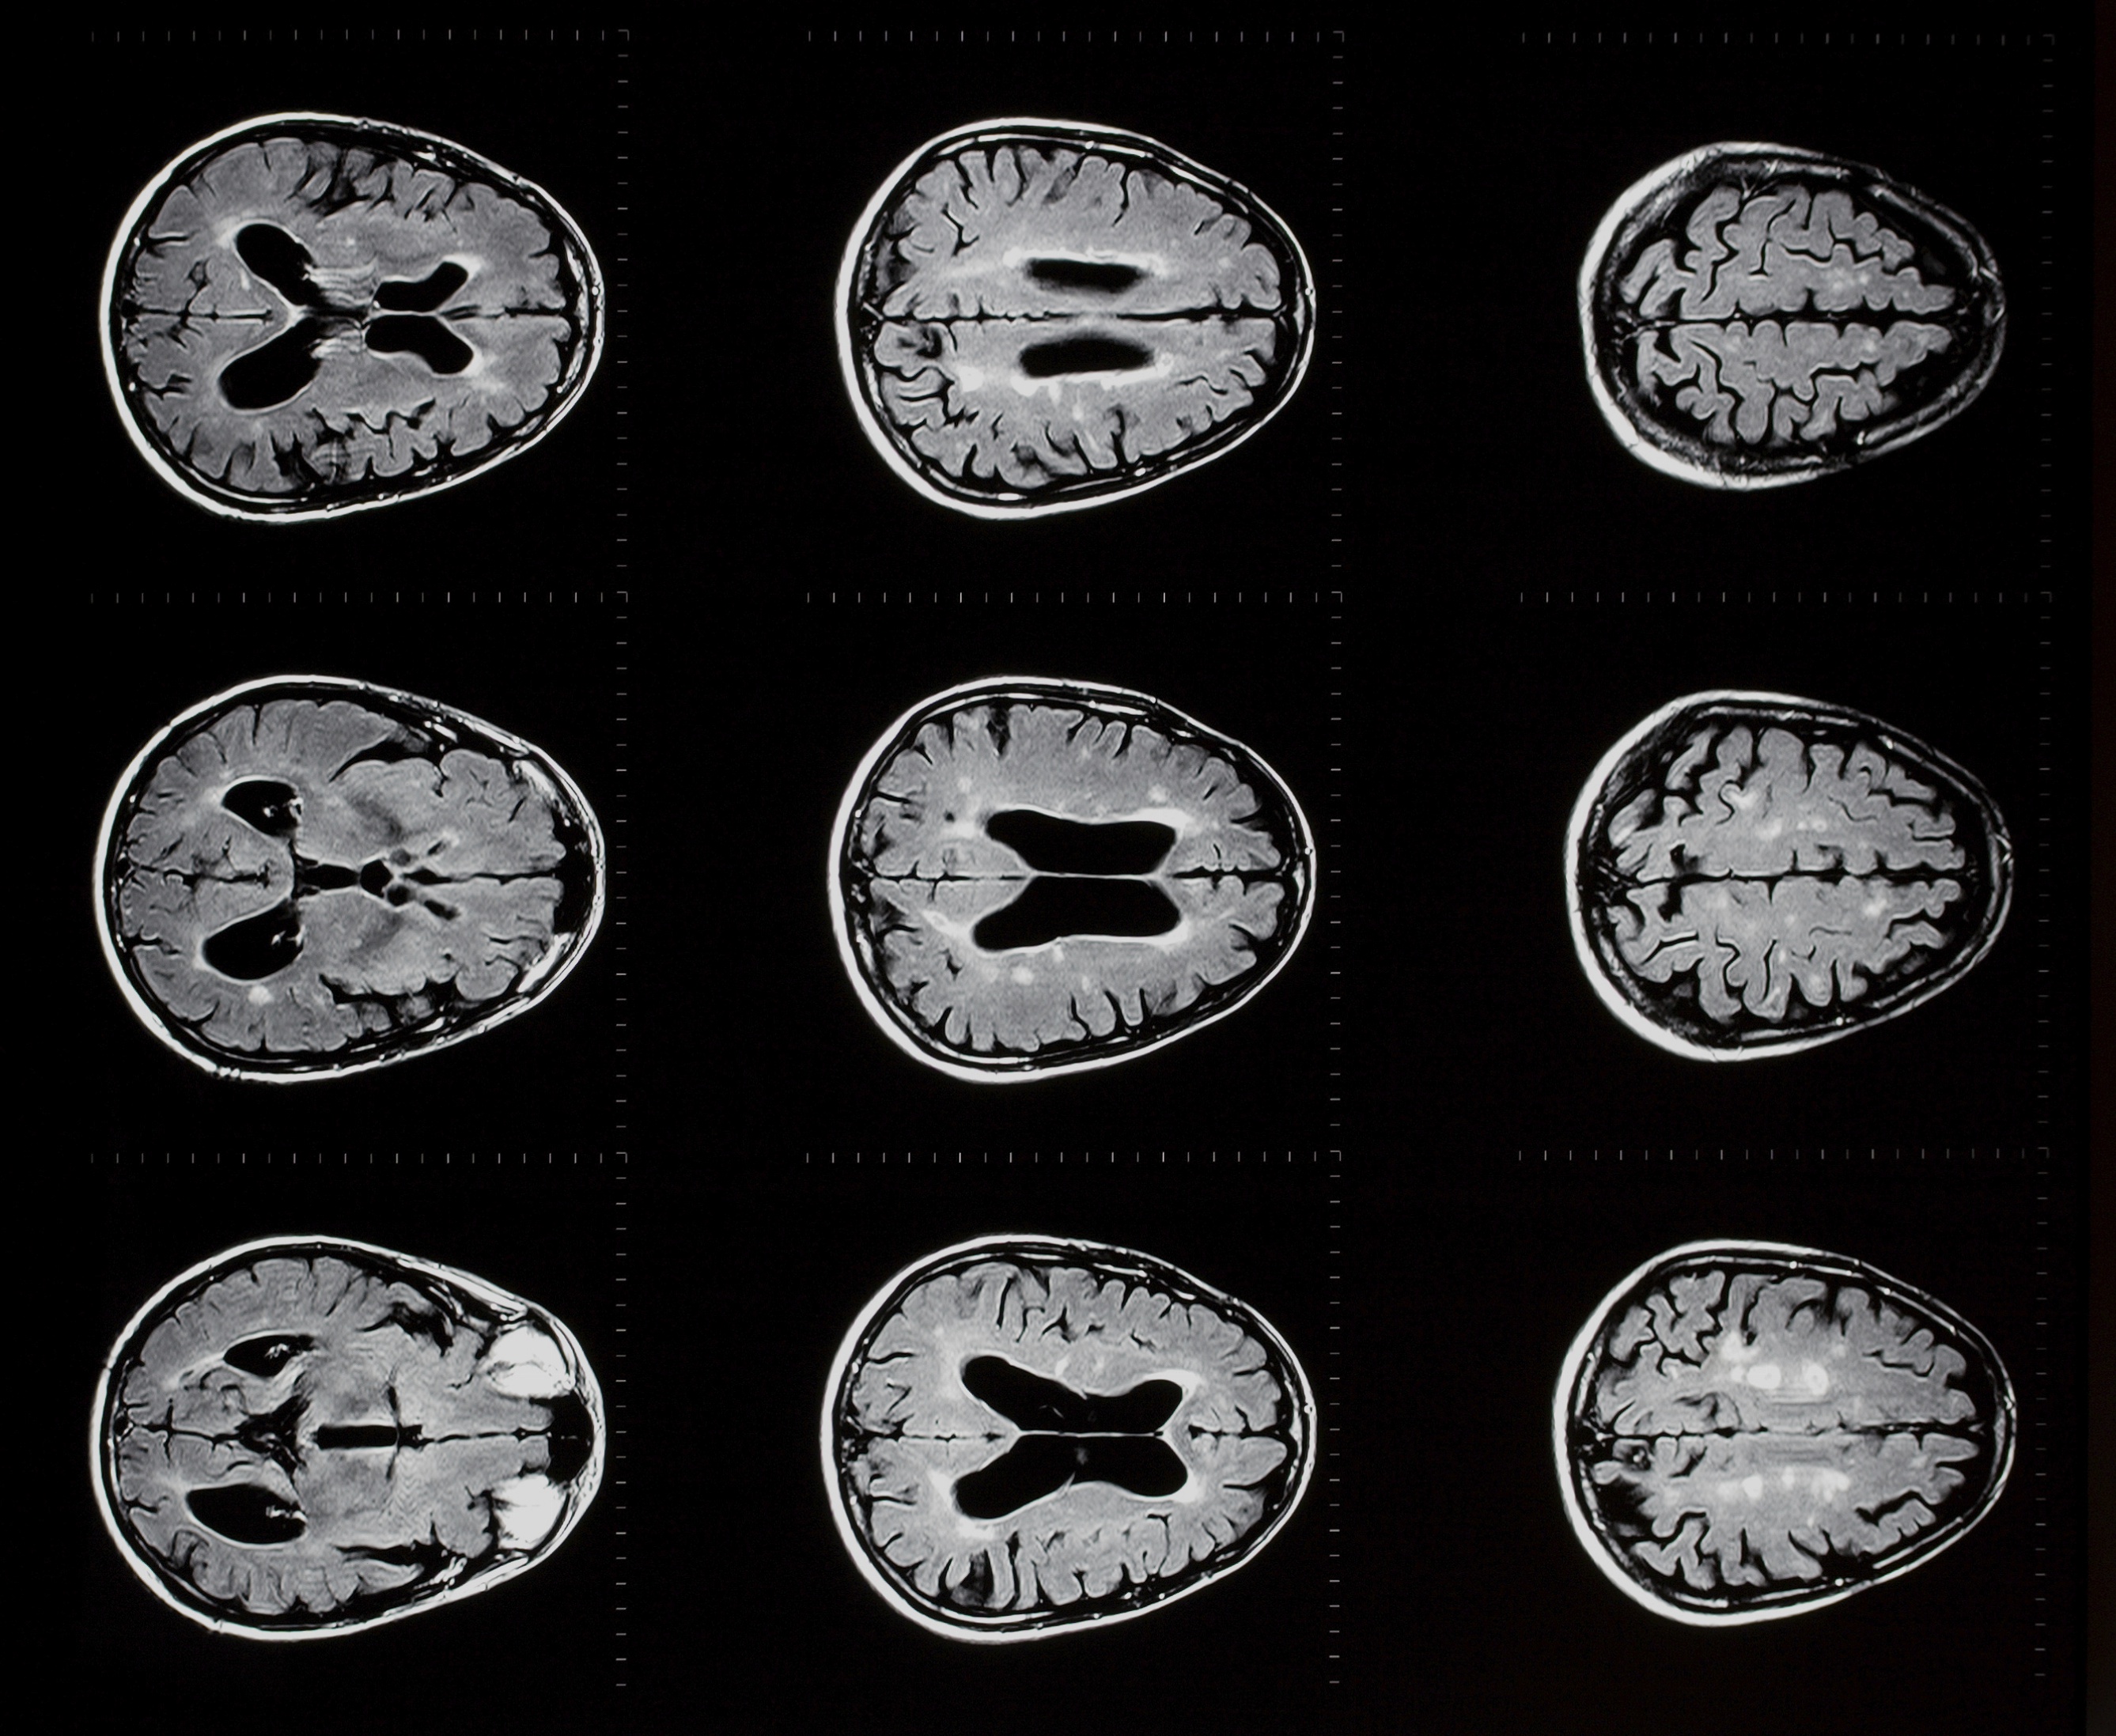

Coma refers to a state of general “brain failure” characterized by severe depression of level of consciousness. Coma outwardly resembles sleep, but is physiologically very different. Sleep is characterized by highly organized and complex electrical brain activity, and can easily be reversed. With stimulation, a sleeping person can be quickly aroused to a state of complete alertness. By contrast, coma is characterized by slowing and depression of electrical brain activity, and implies a neurologic deficit. No matter how much the patient is stimulated, he or she is incapable of becoming fully alert.

Any serious injury to both cerebral hemispheres or the brain stem can produce coma. All causes of coma can be divided into two main categories: (1) structural (e.g. trauma, bleeding, stroke), or (2) toxic/metabolic (e.g. drug overdose, lack of oxygen).

Persistent vegetative state describes the chronic condition that almost invariably emerges after coma. It comprises a return of wakefulness (e.g. eye opening), sleep-wake cycles, and reflex movements (e.g. sucking, startle responses, grabbing), accompanied by a total lack of cognitive or mental activity of any type. The vegetative state is produced by intact function of the brain stem and “deeper” (i.e. subcortical) regions of the brain, without activity of the cerebral cortex itself.